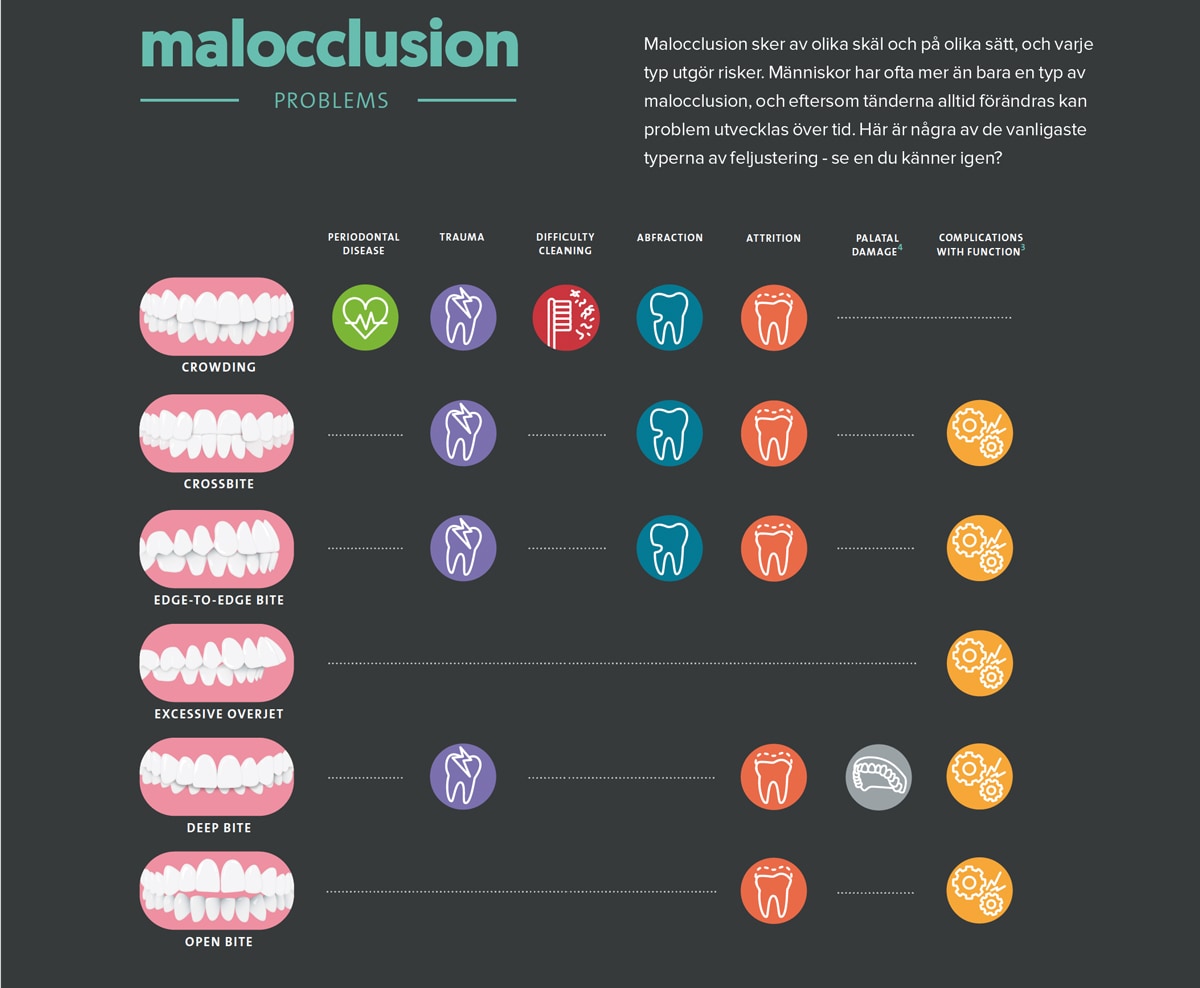

Man skulle kunna tro att det räcker med att ta god hand om sin munhälsa och borsta tänderna två gånger om dagen samt använda tandtråd regelbundet för att slippa problem. Men det stämmer inte alltid, för även om du tar väl hand om dina tänder, kan du dessvärre fortfarande tillhöra riskzonen för karies eller periodontal sjukdom. Tandslitage och käkproblem kan vara exempel på problem som kan ha andra bakomliggande orsaker. Krökta tänder, eller malocclusion, kan vara orsaken till såväl hål som periodontal sjukdom. Att justera tänderna handlar inte bara om att få ett snyggare leende – det kan vara avgörande till förbättrad tandkvalitet och hälsa.

Tänderna är tänkta att passa ihop precis så som kugghjul i en maskin. När de inte linjerar rätt kan maskinen (du, i det här fallet) skada sig själv.